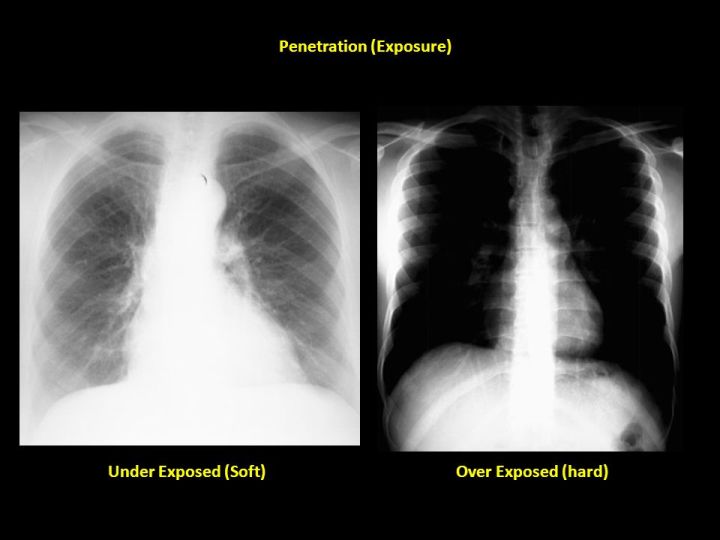

- Penetration: Is the image over or under exposed? Under means the image is too white (the radiation is not getting through adequately and more of the X-ray is appearing white or similar to bone than it should be), and over exposure is too dark. To tell which you have look for the intervertebral disks. Can you see them through the entire duration of the spine? You should need to squint a little in order to make each disk out but but they should NOT be crystal clear. I would dictate this as “appropriate penetration”.